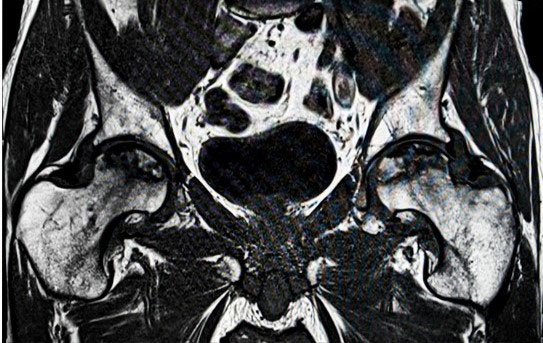

- Anterior Hip Replacement

- Total Hip And Knee Replacements

Avascular Necrosis